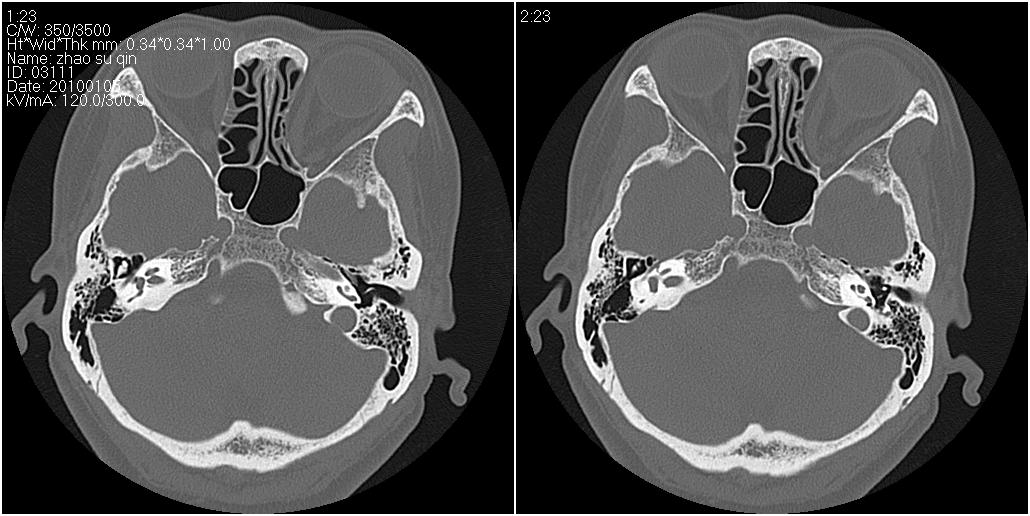

标题: CT24015:一个头部外伤患者进行鉴定,除了左侧筛板骨折,哪 [打印本页]

标题: CT24015:一个头部外伤患者进行鉴定,除了左侧筛板骨折,哪

看了几遍,其余未见明显骨折征。

1)左侧筛板骨折。2)双侧筛窦炎症(或积血)。

请明示骨折部位。